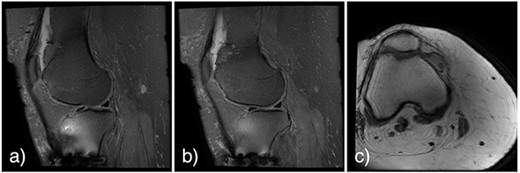

At 2 weeks post-op, the patient was managing pain well, and she demonstrated appropriate range of motion and strength. At 6-week follow-up, however, she complained of diffuse, painful grinding in the right knee which impaired her ability to ambulate. Physical exam revealed audible and palpable crepitus in the knee as well as tenderness to palpation at the medial and lateral joint lines. Radiographs demonstrated unchanged alignment of the tibia fracture (Fig. 3). Multiplanar T1 and T2 MRI without contrast revealed a large full-thickness defect on the lateral femoral trochlea measuring 1.8 cm in diameter with a loose chondral fragment in the superior medial joint space (Fig. 4).

Noncontrast multiplanar T1 (a and b) and T2 (c) MRI at 7 weeks post-op showing a large full-thickness defect on the lateral femoral trochlea measuring 1.8 cm in diameter with a loose chondral fragment in the superior medial joint space.